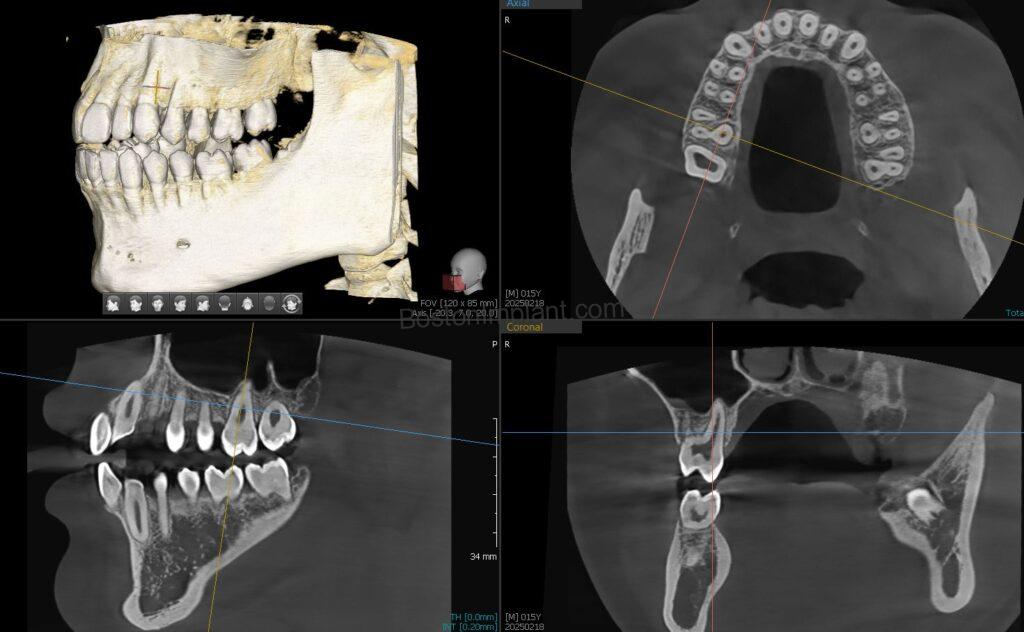

Similarly, with CBCT, multiple 2-dimensional images are combined to create a 3-dimensional image. This allows us to see details that are not visible with conventional X-rays.

1. Planning Dental Implants: By analyzing bone shape in a three-dimensional view, we can find the optimal position and angle for dental implants. After planning, we create a surgical guide to accurately transfer the plan to the actual surgery. (Please check out our information on dental implant surgical guides!)

6. Orthodontics (Invisalign, Clear Aligners, Teeth Straightening): This is a newer application for CBCT in dentistry, but Invisalign and clear aligner patients can greatly benefit. In orthodontics, teeth (specifically their roots) move within the bone. Traditionally, we estimated root shapes based on the visible crown. Now, with 3D root and bone images from CBCT, we eliminate guesswork. This allows for more accurate simulation of root movements, ensuring the best possible outcome for your teeth straightening journey.